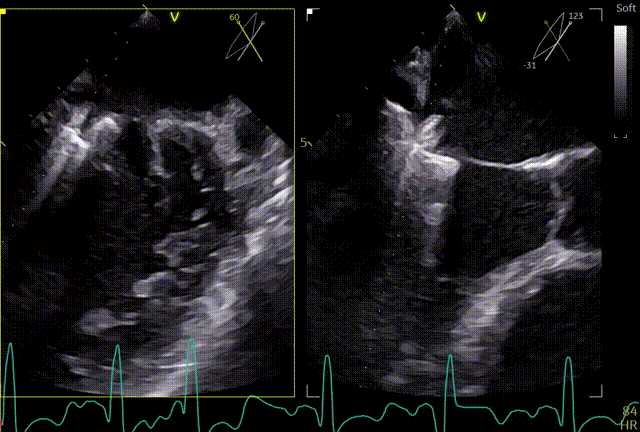

3D

3区gap

术前左房压

术前肺静脉频谱